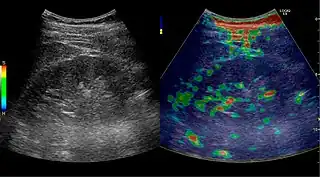

Complex cysts can have membranes dividing the fluid-filled center with internal echoes, calcifications or irregular thickened walls. The complex cyst can be further evaluated with Doppler US, and for Bosniak classification and follow-up of complex cysts, either contrast-enhanced ultrasound (CEUS) or contrast CT is used (Figure 6). The Bosniak classification is divided into four groups going from I, corresponding to a simple cyst, to IV, corresponding to a cyst with solid parts and an 85–100% risk of malignancy.[1] In polycystic kidney disease, multiple cysts of varying size in close contact with each other are seen filling virtually the entire renal region. In advanced stages of this disease, the kidneys are enlarged with a lack of corticomedullary differentiation (Figure 7).[1]

Figure 6. Complex cyst with thickened walls and membranes in the lower pole of an adult kidney. Measurements of kidney length and the complex cyst on the US image are illustrated by '+' and dashed lines.[1]

Figure 31. Unspecific cortical lesion on CT is confirmed cystic and benign with contrast-enhanced ultrasound (CEUS) using image fusion.[1]